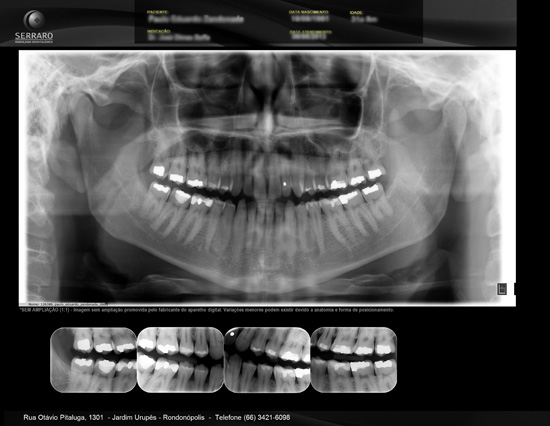

Também chamada de ortopantomográfica. Permite em uma única tomada, a visualização das estruturas do complexo maxilo-facial , conferindo portanto sua utilidade em todas as especialidades. Devido ao posicionamento do paciente (afastado do filme) a imagem não possui a mesma riqueza de detalhes finos como na periapical, porém vantagens como ampla cobertura da área examinada, a projeção das estruturas anatômicas com reduzida superposição , além da baixa dose de radiação, são justificativa de sua crescente aceitação.

• Para Implante

Com o auxílio de um software específico as estruturas anatômicas são evidenciadas e realizamos medidas lineares já corrigindo o valor de ampliação da imagem (específico para cada tipo de aparelho e fabricante).

Exame que compreende de uma radiografia panorâmica e interproximais de molares e pré-molares de ambos os lados.